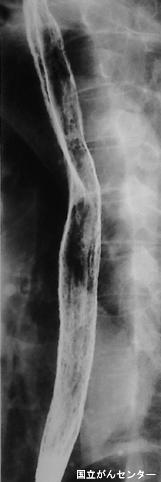

A case of candida esophagitis (moniliasis) associated with advanced gastric cancer.

Tokyo Pref., Cooperative study between National Cancer Center and Kyushu Cancer Center

Inflammatory or ulcerative disease / lesions/candida esophagitis (moniliasis)

Esophagus/More than one of the above

X-ray